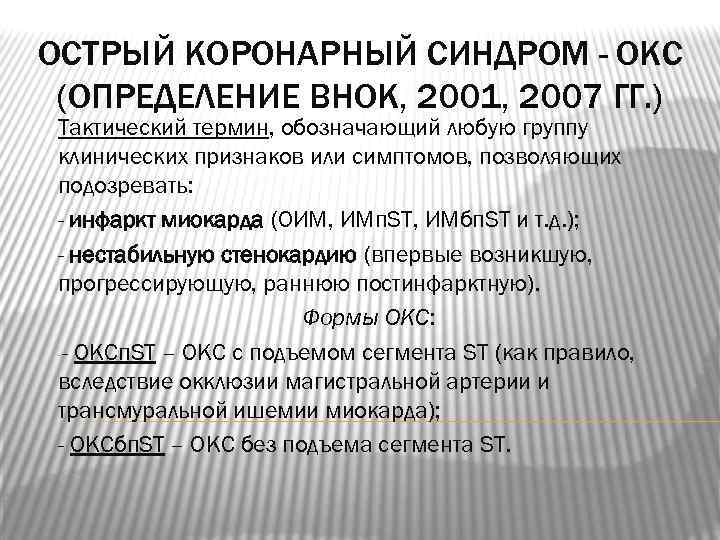

ОСТРЫЙ КОРОНАРНЫЙ СИНДРОМ - ОКС (ОПРЕДЕЛЕНИЕ ВНОК, 2001, 2007 ГГ. ) Тактический термин, обозначающий любую группу клинических признаков или симптомов, позволяющих подозревать: - инфаркт миокарда (ОИМ, ИМп. ST, ИМбп. ST и т. д. ); - нестабильную стенокардию (впервые возникшую, прогрессирующую, раннюю постинфарктную). Формы ОКС: -- ОКСп. ST – ОКС с подъемом сегмента ST (как правило, вследствие окклюзии магистральной артерии и трансмуральной ишемии миокарда); - ОКСбп. ST – ОКС без подъема сегмента ST.

ОСТРЫЙ КОРОНАРНЫЙ СИНДРОМ - ОКС (ОПРЕДЕЛЕНИЕ ВНОК, 2001, 2007 ГГ. ) Тактический термин, обозначающий любую группу клинических признаков или симптомов, позволяющих подозревать: - инфаркт миокарда (ОИМ, ИМп. ST, ИМбп. ST и т. д. ); - нестабильную стенокардию (впервые возникшую, прогрессирующую, раннюю постинфарктную). Формы ОКС: -- ОКСп. ST – ОКС с подъемом сегмента ST (как правило, вследствие окклюзии магистральной артерии и трансмуральной ишемии миокарда); - ОКСбп. ST – ОКС без подъема сегмента ST.